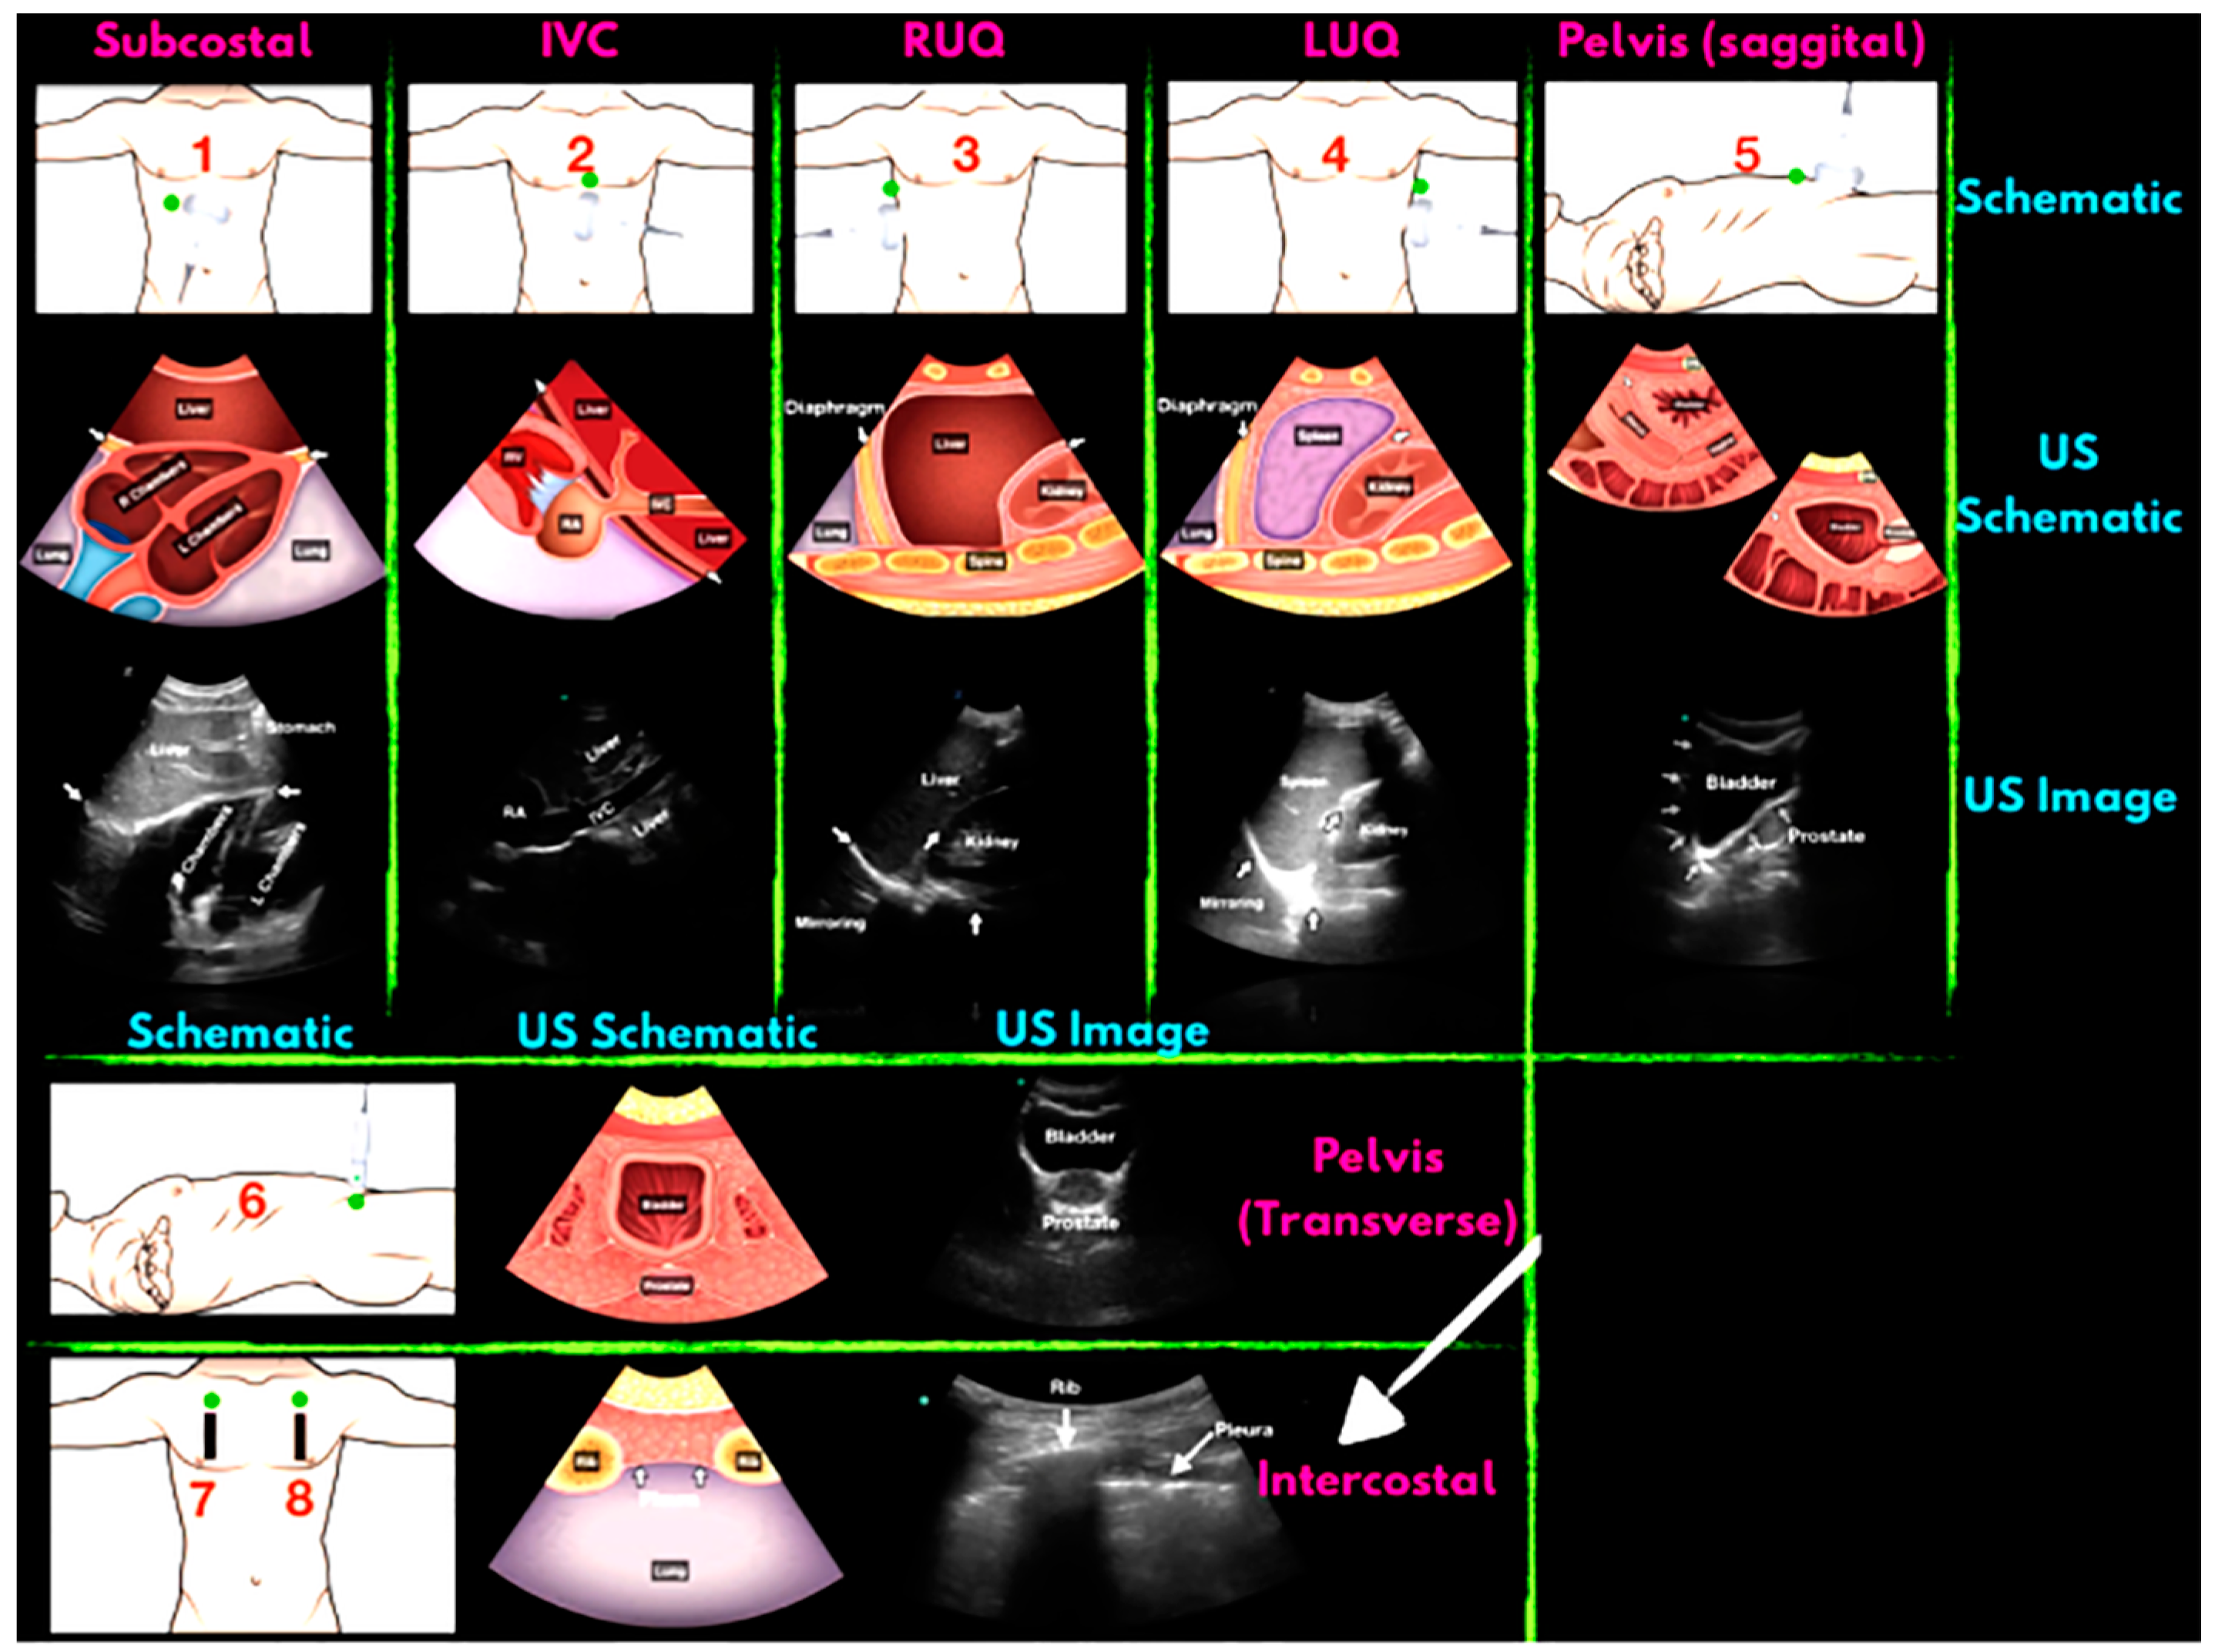

2.2. Application of Portable Intelligent Ultrasound in the Diagnosis of Abdominal Trauma